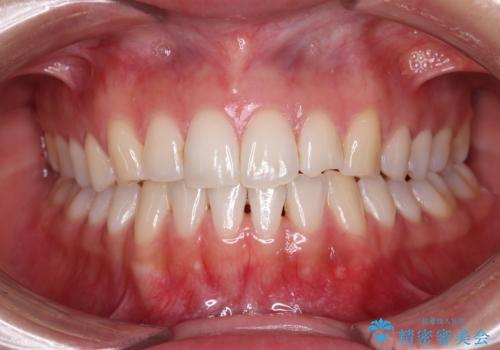

前歯の隙間と上下正中のズレを解消

正中がなかなか合わずに、2年近くの治療期間を要しました。